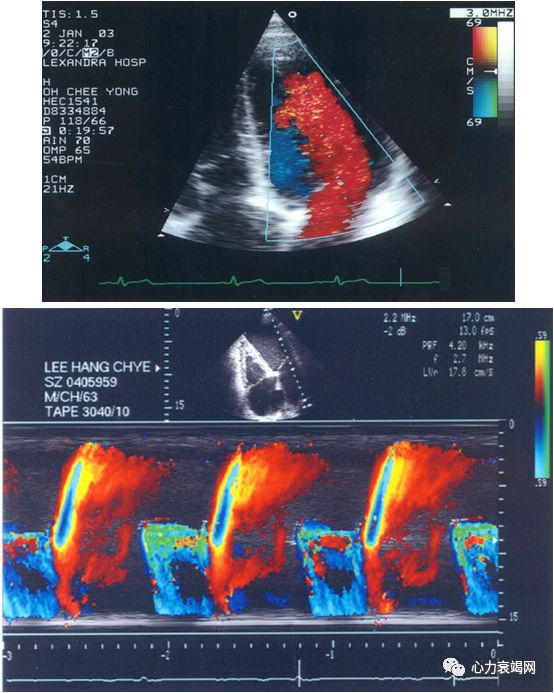

取心尖四腔切面,启动CDFI并调整M型取样线通过二尖瓣口至心尖使之与舒张期充盈血流平行,然后启动M型成像,在窦性心律者显示两个与E和A相关彩色血流,测量舒张早期充盈血流出现彩色混叠颜色变化前缘向心尖方向延伸4cm处的斜率。

E / Vp>1.5 时 LA 压力增高。

AMI 后E / Vp<1.5者的预后明显好于E/ Vp≥1.5者。

有报道E/ Vp预测AMI 后发生心衰及死亡的价值优于EF。